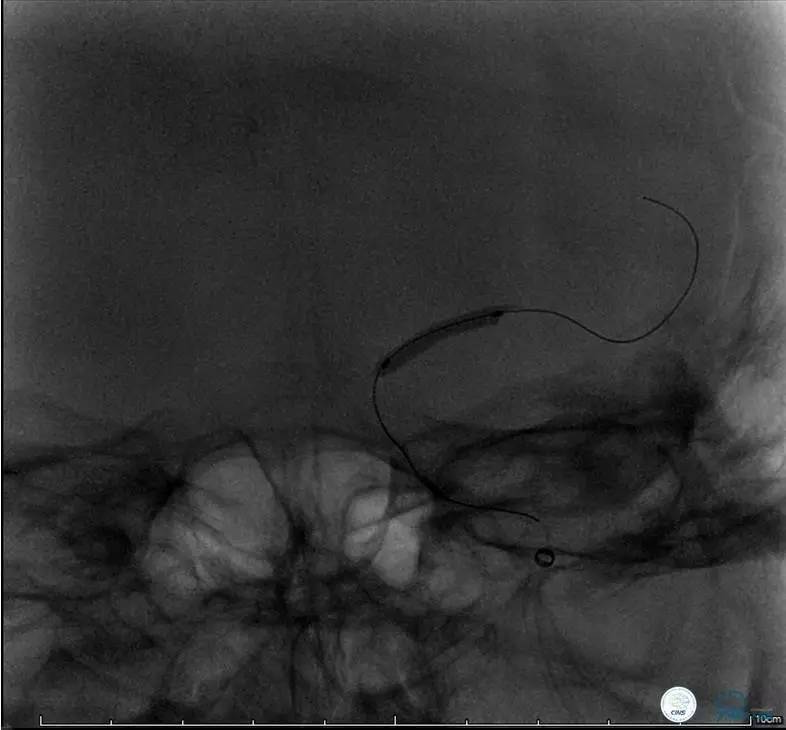

造影评价血管、判断闭塞段,微导丝小心穿过闭塞段,微导管造影,交换技术,球囊扩张,Enterprise支架。在后扩张时导丝刺破M3段血管,蛛网膜下腔出血(SAH)。

微导管进入破裂血管,栓塞弹簧圈1枚,出血停止,结束手术。继续双抗,术后2天肌力2级,神经功能恢复明显加快。